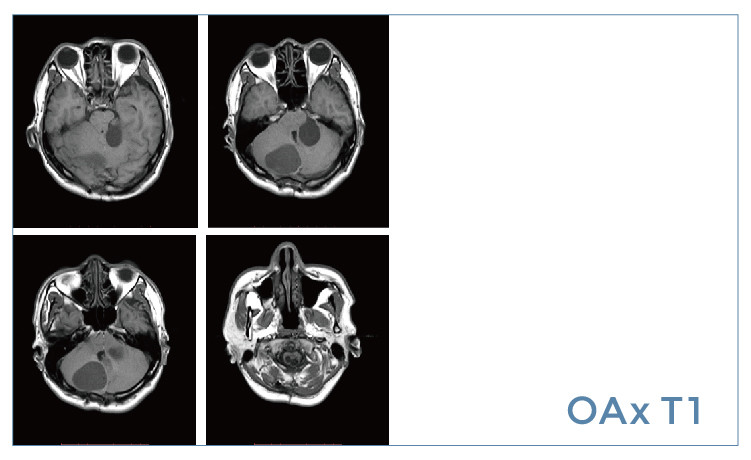

【朗润影像档案】20190621磁共振影像病例结果讨论

【朗润影像档案】磁共振影像病例分享(编号20190621)